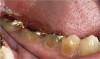

Figure  3  Severe dental erosion and attrition in a GERD patient.

Figure 3